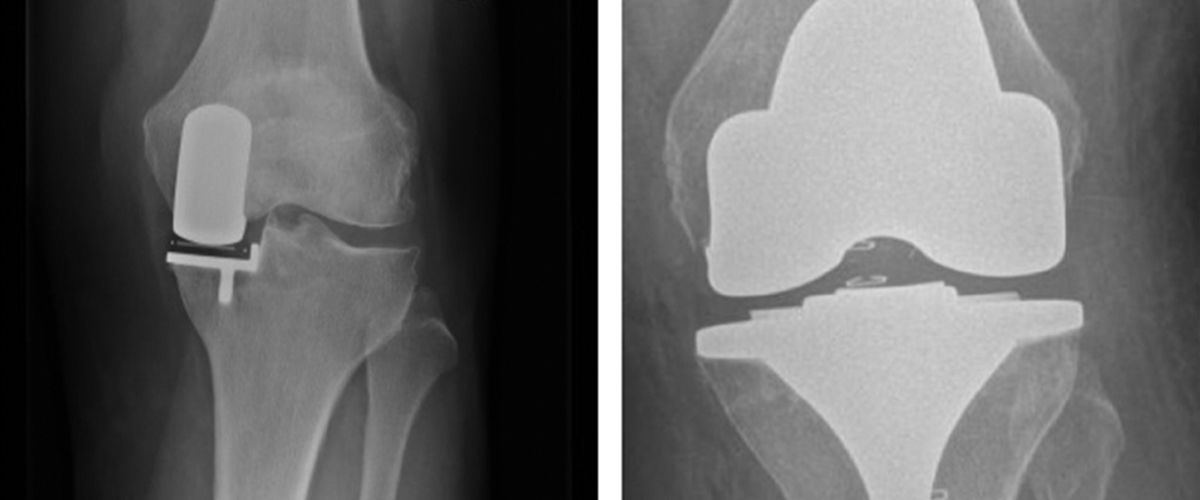

Ortopædkirurgi Lars Blønd har for nyligt udviklet en ny og vellykket operationsteknik til behandling af Artroscopisk Trokleoplastik, der udføres med en kikkertoperation.